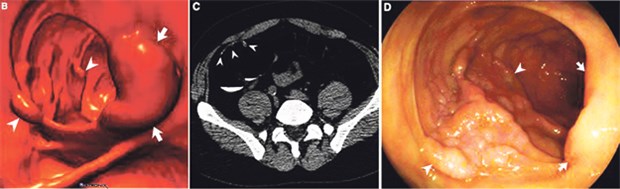

Lateral wachsender Tumor in der CT-Koloskopie (CTC) und der optischen Koloskopie (OC). Darstellung in der 3D CTC (B), in der 2D CTC (C) sowie in der OC (D). Zu sehen ist eine große gelappte Läsion (Pfeilspitzen), die aufgrund ihrer Masse eine chirurgische Resektion erforderlich machte.